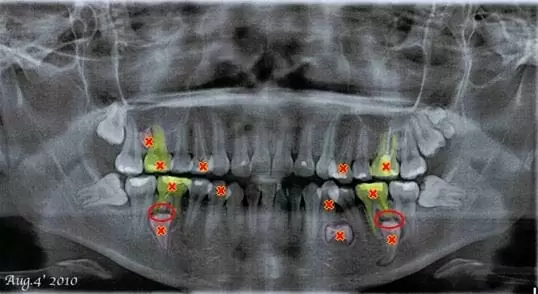

經曾醫師透過X光片診斷發現病症,病人屬於罕見的增生牙病況,(增生牙會導致正常成人牙齒的牙根產生破骨細包,而使牙根產生外吸收現象,病患到了約40多歲左右會因牙根的外吸收,造成牙齒不穩固、搖動的現象。

圖1.轉口腔外科將埋在骨頭裏的增生牙取出,並拔掉已產生牙根外吸收的牙齒及其他已長出的增生牙。

拔掉埋在骨頭裏的增生牙以及已經產生牙根外吸收的牙齒。